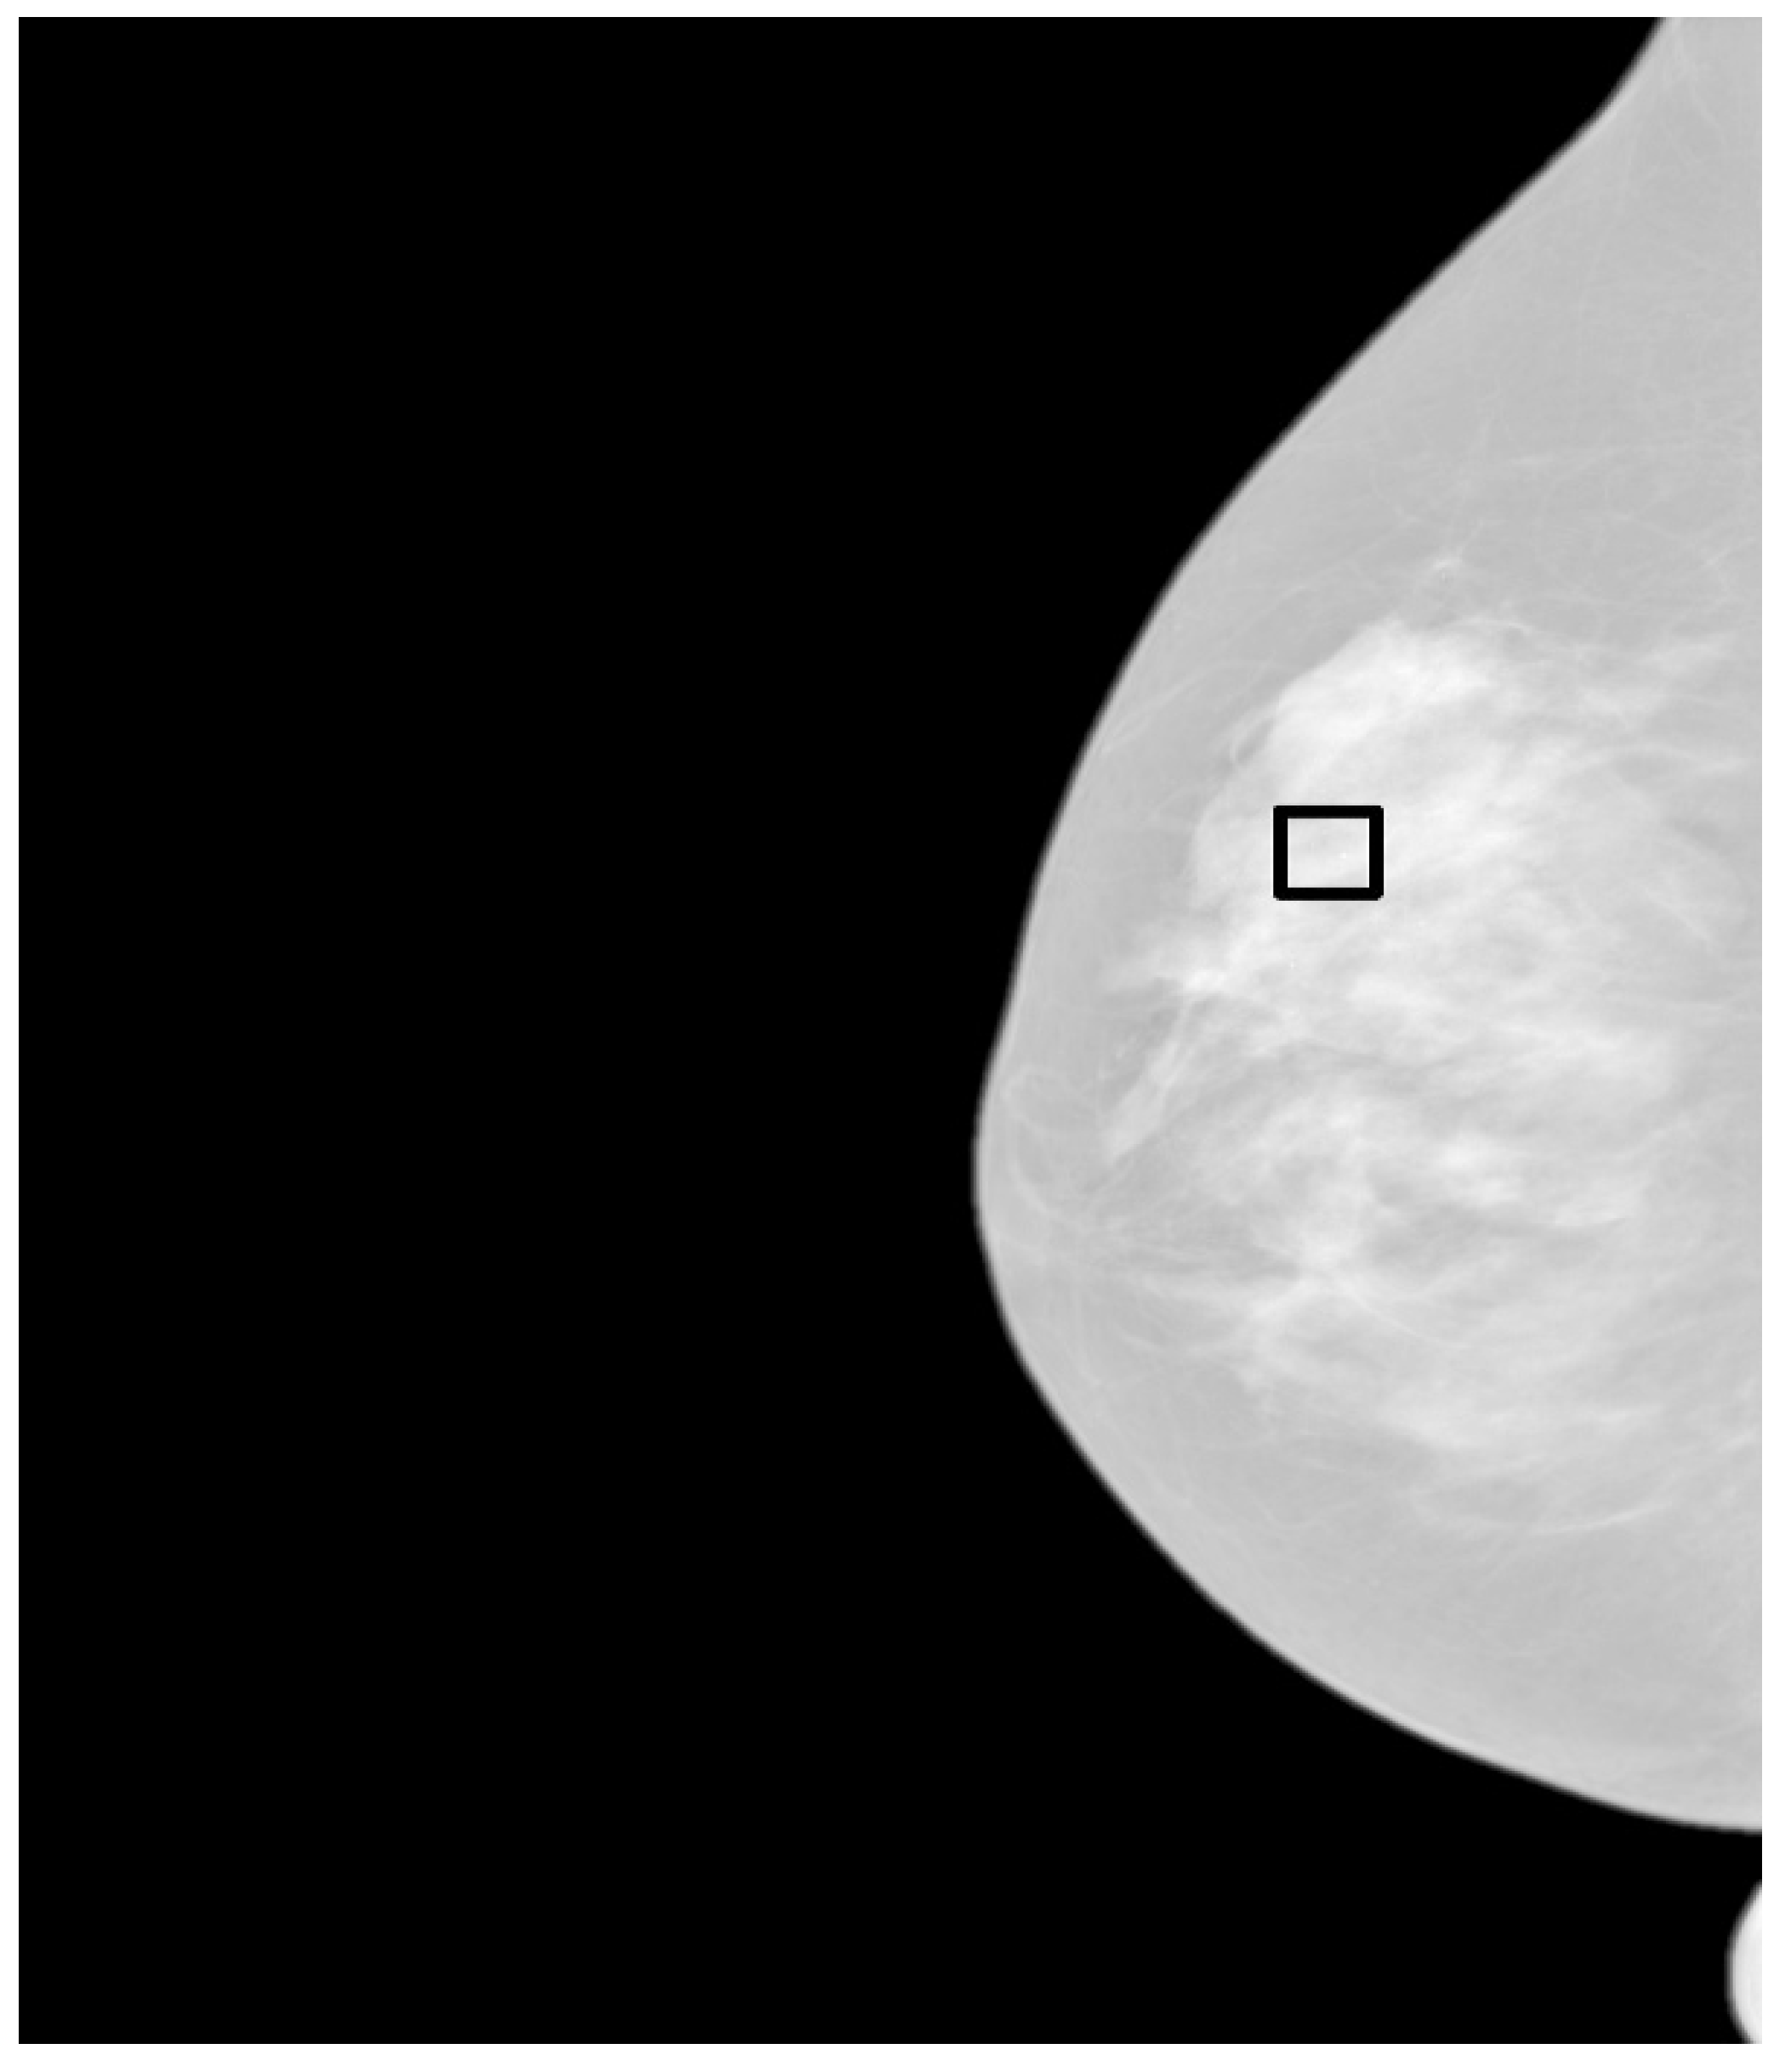

- Zoom the region of interest of the image around the microcalcification clusters. Use simple nearest neighbor zooming without interpolation.

- Use a complete set of fractal filters for pixel diffusion. Convolve each fractal mask with the original ROI. A very good zooming factor is × 8 when a set of fractal masks composed of 5 × 5 pixels is used, with angular increments of 45 degrees from 0 to 315 degrees.